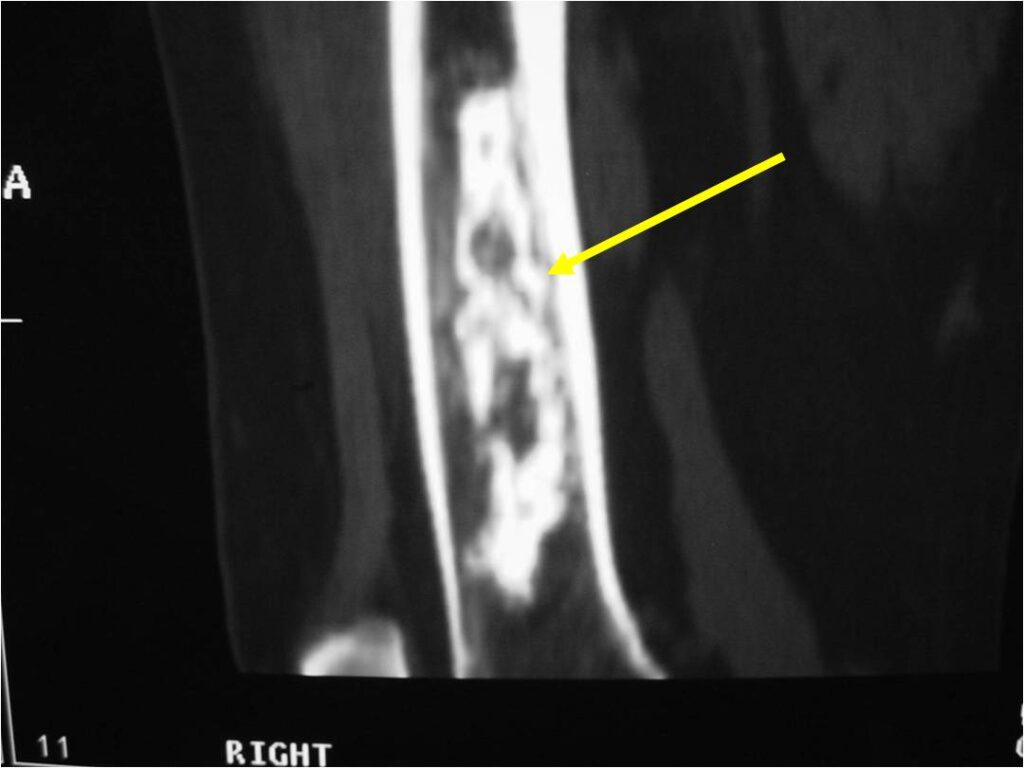

MRI:

- Lobulated margin (Lobular Growth Pattern)

- T1 Weighted Images: Intermediate Signal Intensity

- Calcifications will be low signal

- T2 Weighted Images: High Signal Intensity

- High water content shows as high signal on T2 weighted images

- Marked increased intensity long TR images

- Calcified chondroid – low intensity all sequences

- There should never be any cortical destruction nor a soft tissue component. If this exists then the tumor must be a chondrosarcoma.

- Endosteal scalloping and cortical expansion is acceptable for phalangeal tumors. In most benign long bone cartilage tumors there is minimal endosteal scalloping but there should be no cortical expansion nor thickening. There should be no cortical destruction and no soft tissue component associated with an enchondroma. Cortical destruction, periosteal thickening, cortical expansion and a soft tissue component indicates a chondrosarcoma of the long bone.

Metaphyseal Tumor, Heavy Calcifications, Ring and Arc Pattern of Calcifications, Minimal Endosteal Scalloping, No Cortical Destruction, No Periosteal Reaction, No Cortical Destruction, No Soft Tissue Component

Metaphyseal Tumor, Heavy Calcifications, Ring and Arc Pattern of Calcifications, Minimal Endosteal Scalloping, No Cortical Destruction, No Periosteal Reaction, No Soft Tissue Component